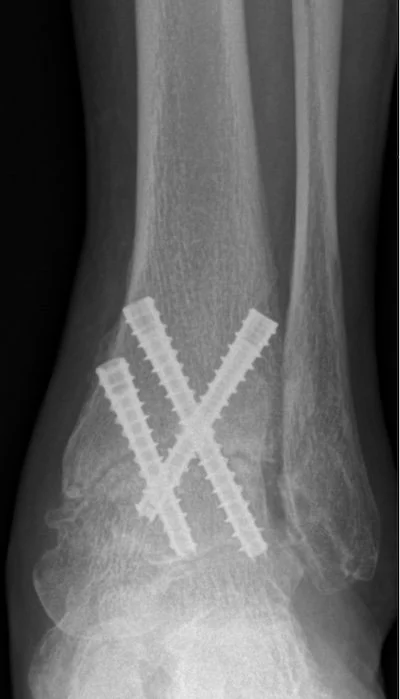

ARTHRODESIS ( JOINT FUSION )

Some conditions necessitate the removal of a joint. when we remove a joint one option is to attach the remaining bones to each other and to let them heal into one larger bone. This does stop any motion that the joint had before the surgery but when it comes to the foot or ankle that loss of motion may not be too noticeable to the patient. We perform fusions for situations where there is significant arthritis and cartilage damage in a joint that cannot be salvaged. Click here: ARTHRITIS SURGERY to learn more about other techniques we can use to avoid fusion. The good thing about arthrodesis or joint fusion is the fact that it works well in most cases without significant complications in most cases. (of course this depends on the skill and experience of the surgeon and the overall medical condition of the patient). The other good thing is that its outcomes are predictable- the fused joint should remain in the position that it was placed into. Another reason we use this fusion technique is to correct deformities like in the case of FLATFOOT or CLUBFOOT.

During the surgery , once the joint is prepared for fusion. Hardware must be placed - these surgical implants will hold the bones together while they heal into each other. The types of implants placed depend on the surgeons preference and on the procedure location. Screws , pins, plates or external scaffolds can be used for this.

A common question we get is : Does the screw need to be removed? answer is No unless it bothers the patient. The implants are usually buried deep into the bone and can stay inside.

What are these implants made out of? Modern surgical screws are usually made from titanium, occasionally some made from surgical stainless steel are used. Modern plates are made from either titanium or stainless steel. Also there are a few screws and pins that are available for the surgeon to use that are made out of an absorbing material- and yes over time they are absorbed by the body and disappear. ( not commonly used nowdays)